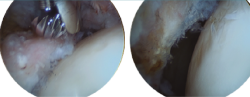

Retiraremos los osteofitos con una fresa desde la unión capsulolabral para movernos más cómodos y seguiremos con la resección del os labrale, osteofito o labrum calcificado (Figura 3).

Figura 3. Paciente con osteofito en el reborde acetabular (imagen izquierda). Resección del osteofito en el reborde acetabular (imagen derecha).